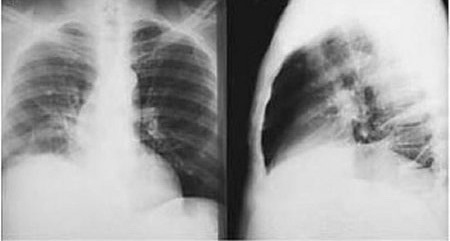

Posterior-anterior and lateral CXR of a patient with amebic liver abscess: CXR findings include elevated right hemidiaphragm and evidence of atelectasis

Reproduced from New England Journal of Medicine (2003); used with permission